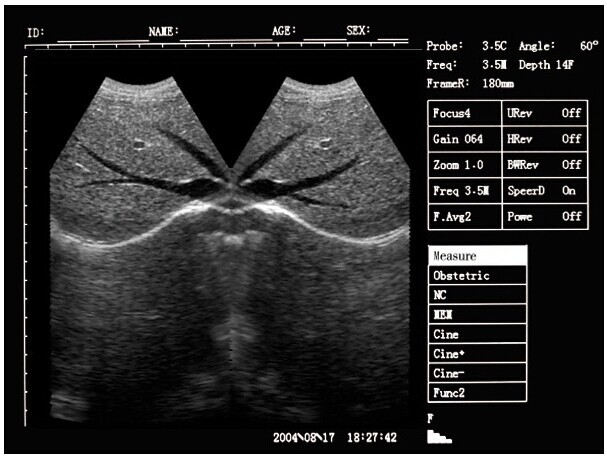

Portable ultrasound machine Laptop Ultrasound machine SU-7S with CE Images |